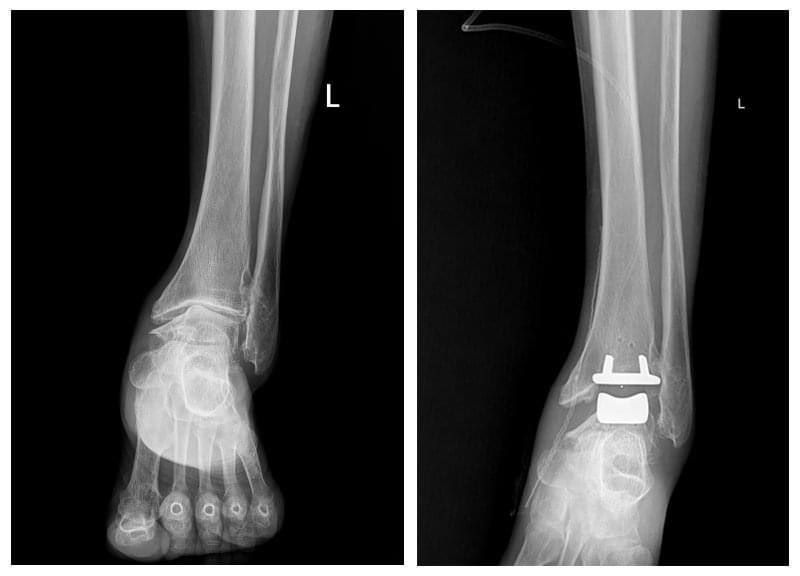

ГССҮТ-ийн Насанд хүрэгсдийн мэс заслын тасгийн их эмч Ш.Баасансүрэнгээр ахлуулсан, тус тасгийн эрхлэгч Б.Баатаржав, Г.Бадамгарав нарын мэс заслын баг бүрэлдэхүүн шагайн үений хүнд хэлбэрийн артроз өөрчлөлтийн үед хиймэл үе суулгах мэс заслыг хийж, орчин үеийн дэвшилтэт мэс засал эмчилгээг тусламж үйлчилгээнд бүрэн нэвтрүүлээд байна.

Тус тасгийн хамт олон 2022 оны арваннэгдүгээр сард БНСУ-ын “Йонсей Гунвоо” эмнэлгийн захирал Eui Hyun Park болон бусад эмч, мэргэжилтнүүдтэй хамтран Монголд анх удаа шагайн хиймэл үе солих мэс заслыг хийсэн бөгөөд 2023 оны арванхоёрдугаар сараас эхлэн энэхүү мэс засал эмчилгээг бие даан амжилттай хийж буй юм.

Шагайн үений хүнд хэлбэрийн артроз өөрчлөлтийн үед хиймэл үе суулгах мэс заслыг Монголд нутагшуулснаар энэ төрлийн шалтгаант өвчлөл, зовиураар шаналж буй иргэд үйлчлүүлэгчид олон улсын стандартыг хангасан тусламж үйлчилгээг эх орондоо, бага зардлаар илүү хялбар, чанар хүртээмжтэй авах, амьдралын чанараа дээшлүүлэх зэрэг таатай боломж бүрдэж байна.